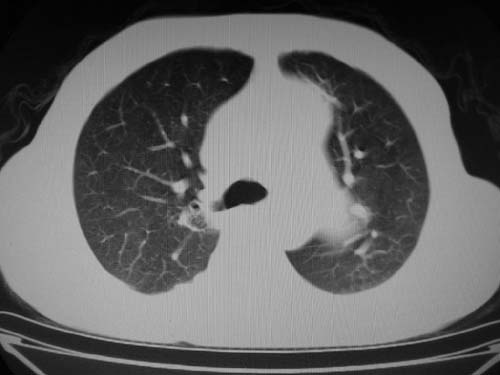

1)考虑肺动脉狭窄。2)右肺上叶继发性肺结核。3)右侧胸膜增厚、钙化,左侧胸膜反应。

左肺动脉异常增粗,考虑肺动脉狭窄可能。

右肺上叶继发性肺结核。

右侧胸膜增厚、钙化,左侧胸膜反应。